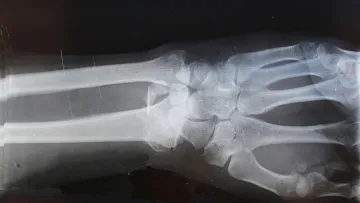

X-ray image showing the bones of a human wrist and lower forearm including radius and ulna.

X-Ray

Many of our patients will require an X-Ray prior to seeing a provider. X-Ray appointments are scheduled approximately 15 minutes prior to your appointment time with the doctor. One of our roomers or staff will direct you to the X-Ray area as appropriate. For lower body injuries, please plan to wear shorts.